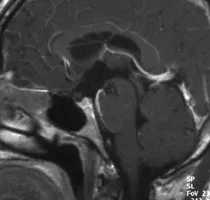

在寻找施罗德教授后,该患者向他叙述了自己的病史。他出现的主要症状包括疲劳、性能下降和勃起功能障碍,双颞侧偏盲。对于颅咽管瘤,磁共振成像(MRI)是首选的检查方法。该患者的MRI显示鞍上颅咽管瘤,肿瘤侵入第三脑室。内分泌检查显示垂体功能部分不足。

使用对比剂的T1加权矢状和冠状MRI图像显示鞍上和室内的颅咽管瘤(双颞侧偏盲)